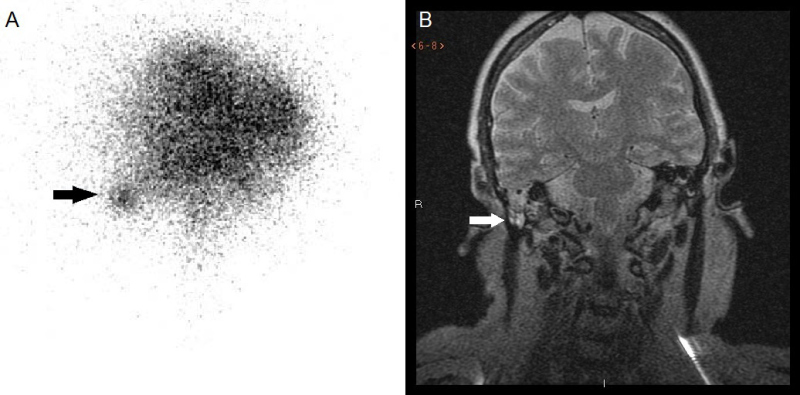

Presentamos imágenes de una paciente de 65 años en estudio por otalgia derecha con pérdida completa de la audición tras proceso gripal, con implante de tubo de drenaje transtimpánico. Posteriormente, inició otorrea abundante de líquido transparente, instaurándose tratamiento antibiótico ante la posibilidad de fuga de LCR. Mediante TC craneal se identificó una ocupación del oído medio, espacio de Prussak y receso hipotimpánico, con erosión del scotum y del tegmen timpani por probable colesteatoma (figura 1b, flecha). La exploración neurológica no demostró afectación meníngea, realizándose una cisternogammagrafía isotópica con 111In-DTPA ante la persistencia de la otorrea y sospecha de fístula de LCR, presentando actividad intensa del radiofármaco en oído derecho y en todos los tapones óticos (figura 2A, flecha). Una RNM cerebral posterior no mostró signos de encefalocele ni meningocele (figura 2B, flecha). Tras la confirmación de la existencia de fuga de LCR se instaló un drenaje externo lumbar conectado a circuito de depósito hermético y estéril, cediendo la otorrea, sin requerirse intervención quirúrgica.